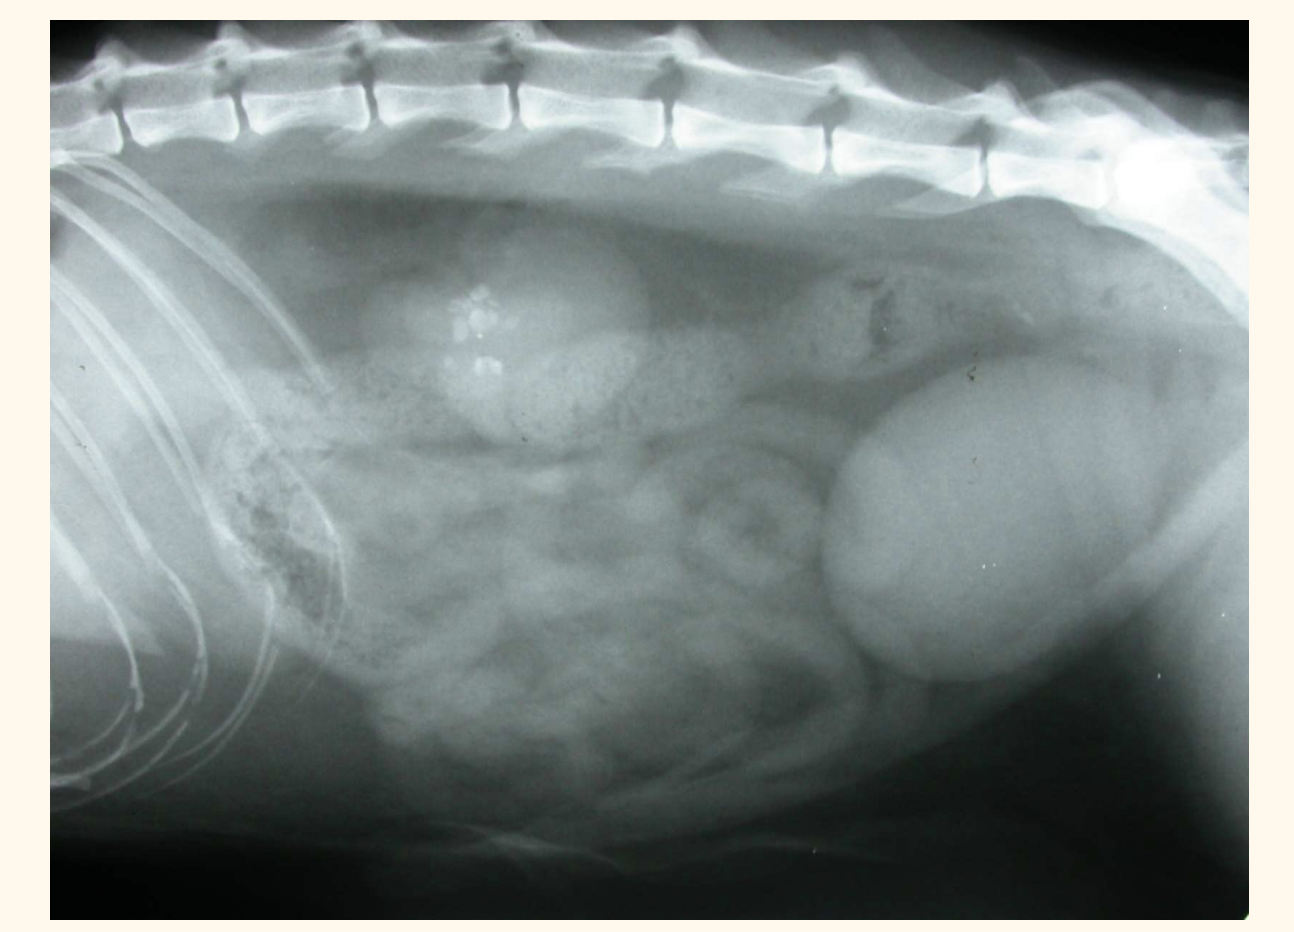

contrast radiography. what does this px have

air -ve contrast

whats wrong with this patient

ectopic ureter— hydroureter